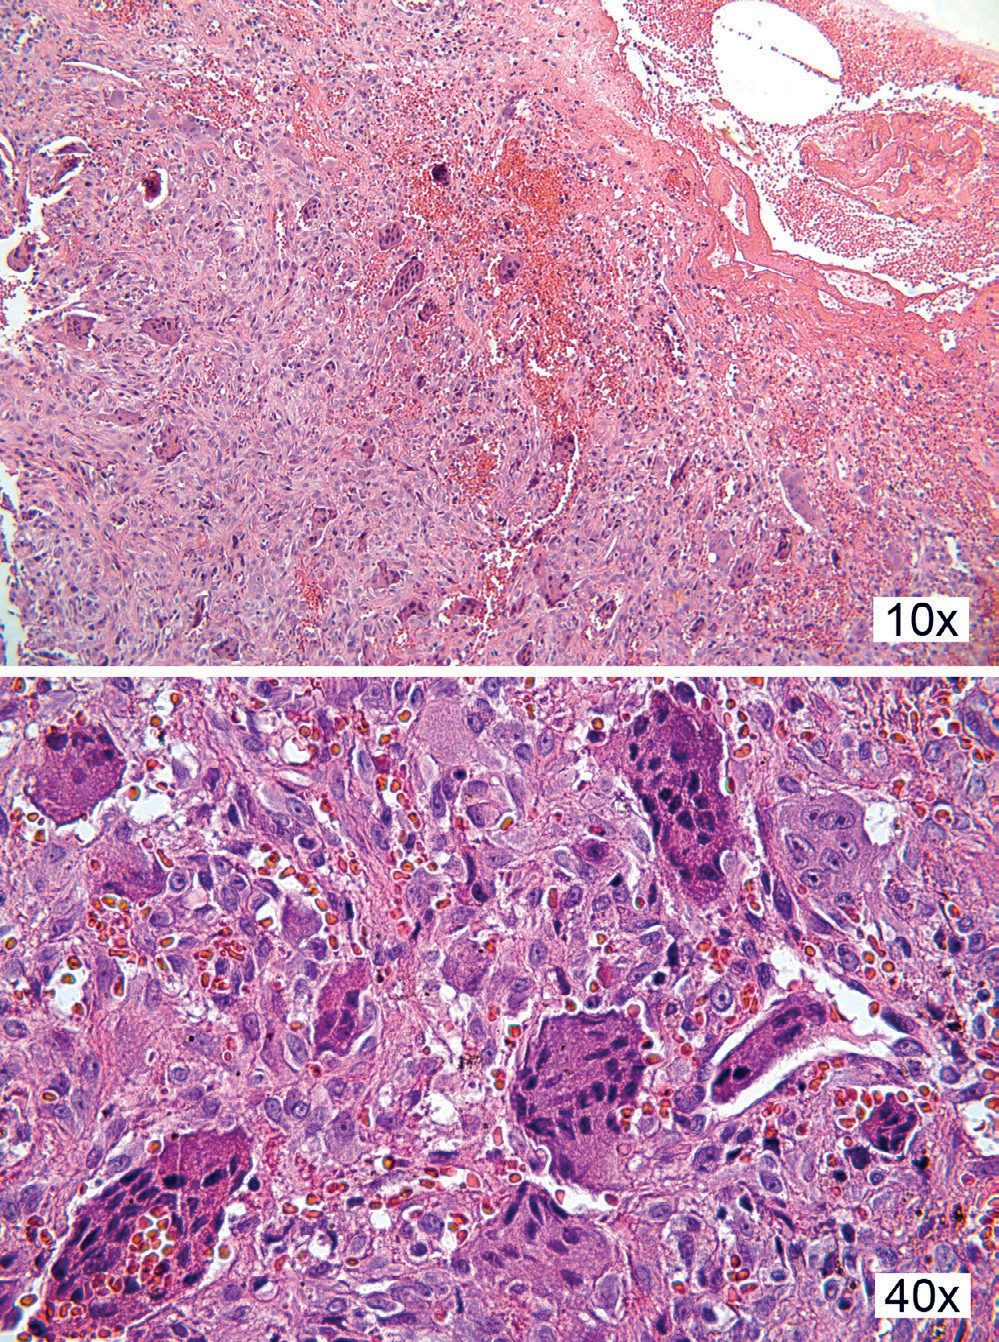

Histologi

Histologisk er bildet relativt ensartet, karakterisert med en bredbaset utvekst kledd av et flerlaget plateepitel som er typisk for gingiva. Epitelet kan eventuelt være hyperplastisk fortykket og med hyperkeratose, særlig dersom det har vært kronisk irritasjon i området. I enkelte tilfeller er forandringene ulcerert, og da sees et brudd i epitelet i det mest prominente området, og tilgrensende bindevev er infiltrert av betennelsesceller (figur 13 10x). I stroma ligger flerkjernede kjempeceller omgitt av tallrike mononukleære celler og mange små blodkar (figur 13 10x, 40x). Disse forandringene sees i mange tilfeller helt ned mot reseksjonsranden, og i slike tilfeller kan det gjerne forekomme residiv senere.

Figur 13. Kasus 15. Histologiske bilde viser ulcerert overflate med blødning og betennelsesceller i overflaten, mens det i underliggende stroma sees tallrike flerkjernete kjempeceller (10x). Nærbilde av de flerkjernede kjempecellene, som er omgitt av tallrike kapillærer og et cellerikt stroma (40x).